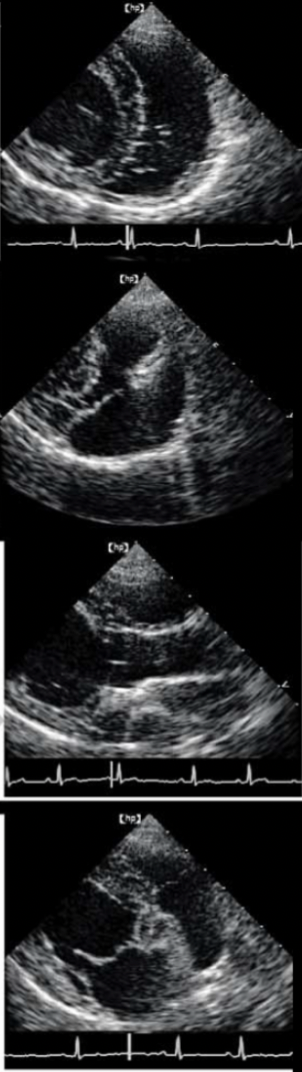

Name the ECHO VIEW and STRUCTURES

RPS LONG AXIS

LPS SHORT AXIS